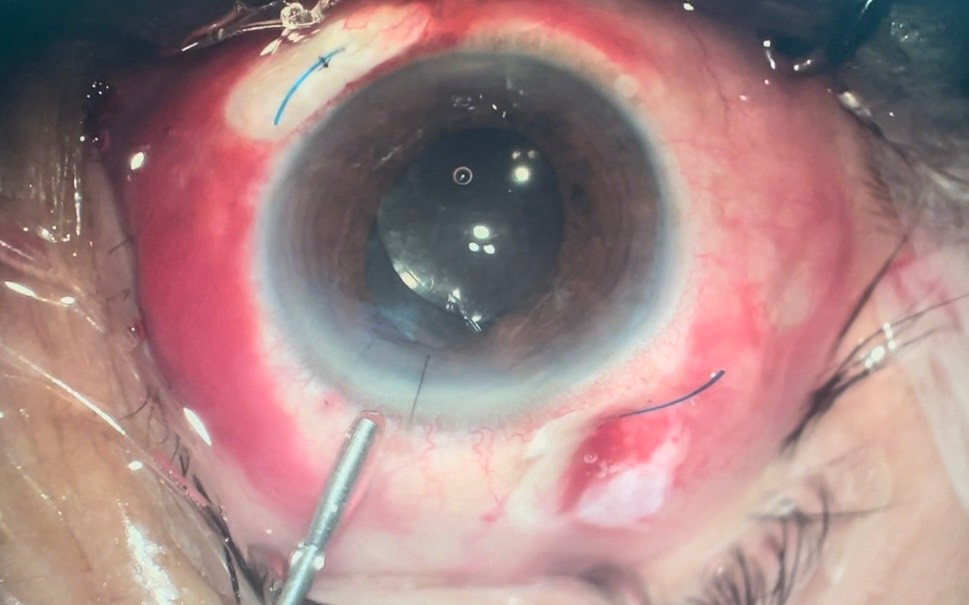

+ Phẫu thuật lấy thủy tinh thể bị lệch và cố định thủy tinh thể nhân tạo

| TTT bị lệch (không hoàn toàn) | Phẫu thuật cố định IOL | Sau phẫu thuật |